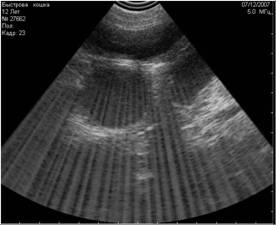

![]() |

Рис. 8. На снимке представлен гиперэхогенный объект в полости мочевого пузыря, испускающий эхоакустическую тень. На основании этого артефакта, мы можем предположить, что этот объект является конкрементом. |

Рис. 9. На снимке представлен похожий по величине и эхогенности объект в полости мочевого пузыря, не испускающий эхоакустической тени. На основании этого признака, мы можем предположить, что изучаемый объект является новообразованием. |